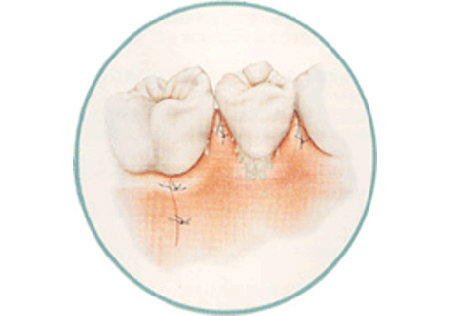

歯周外科治療

麻酔をして少し歯茎を開いてあげると、歯周病菌を目で見て除去することが可能になり、徹底的に歯周病菌を除去できます。また格段に歯周病治療の成績が向上します。条件が揃えば、失ってしまった骨を増やすような再生治療を行うことも可能です。